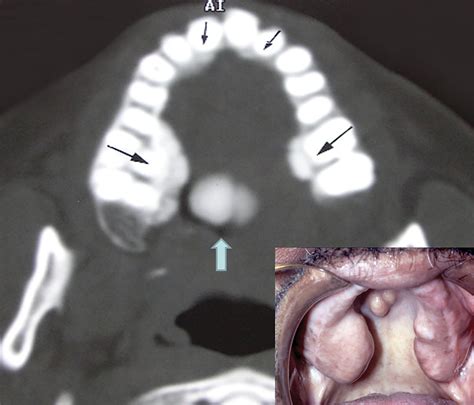

• Torus Palatinus: These occur on the roof of the mouth (hard palate), usually in the center. They can range from flat and wide to lobulated and prominent.

• Torus Mandibularis: These appear on the lingual (tongue-side) aspect of the lower jaw, usually above the mylohyoid line. These are often bilateral, meaning they appear on both the left and right sides of the lower jaw.